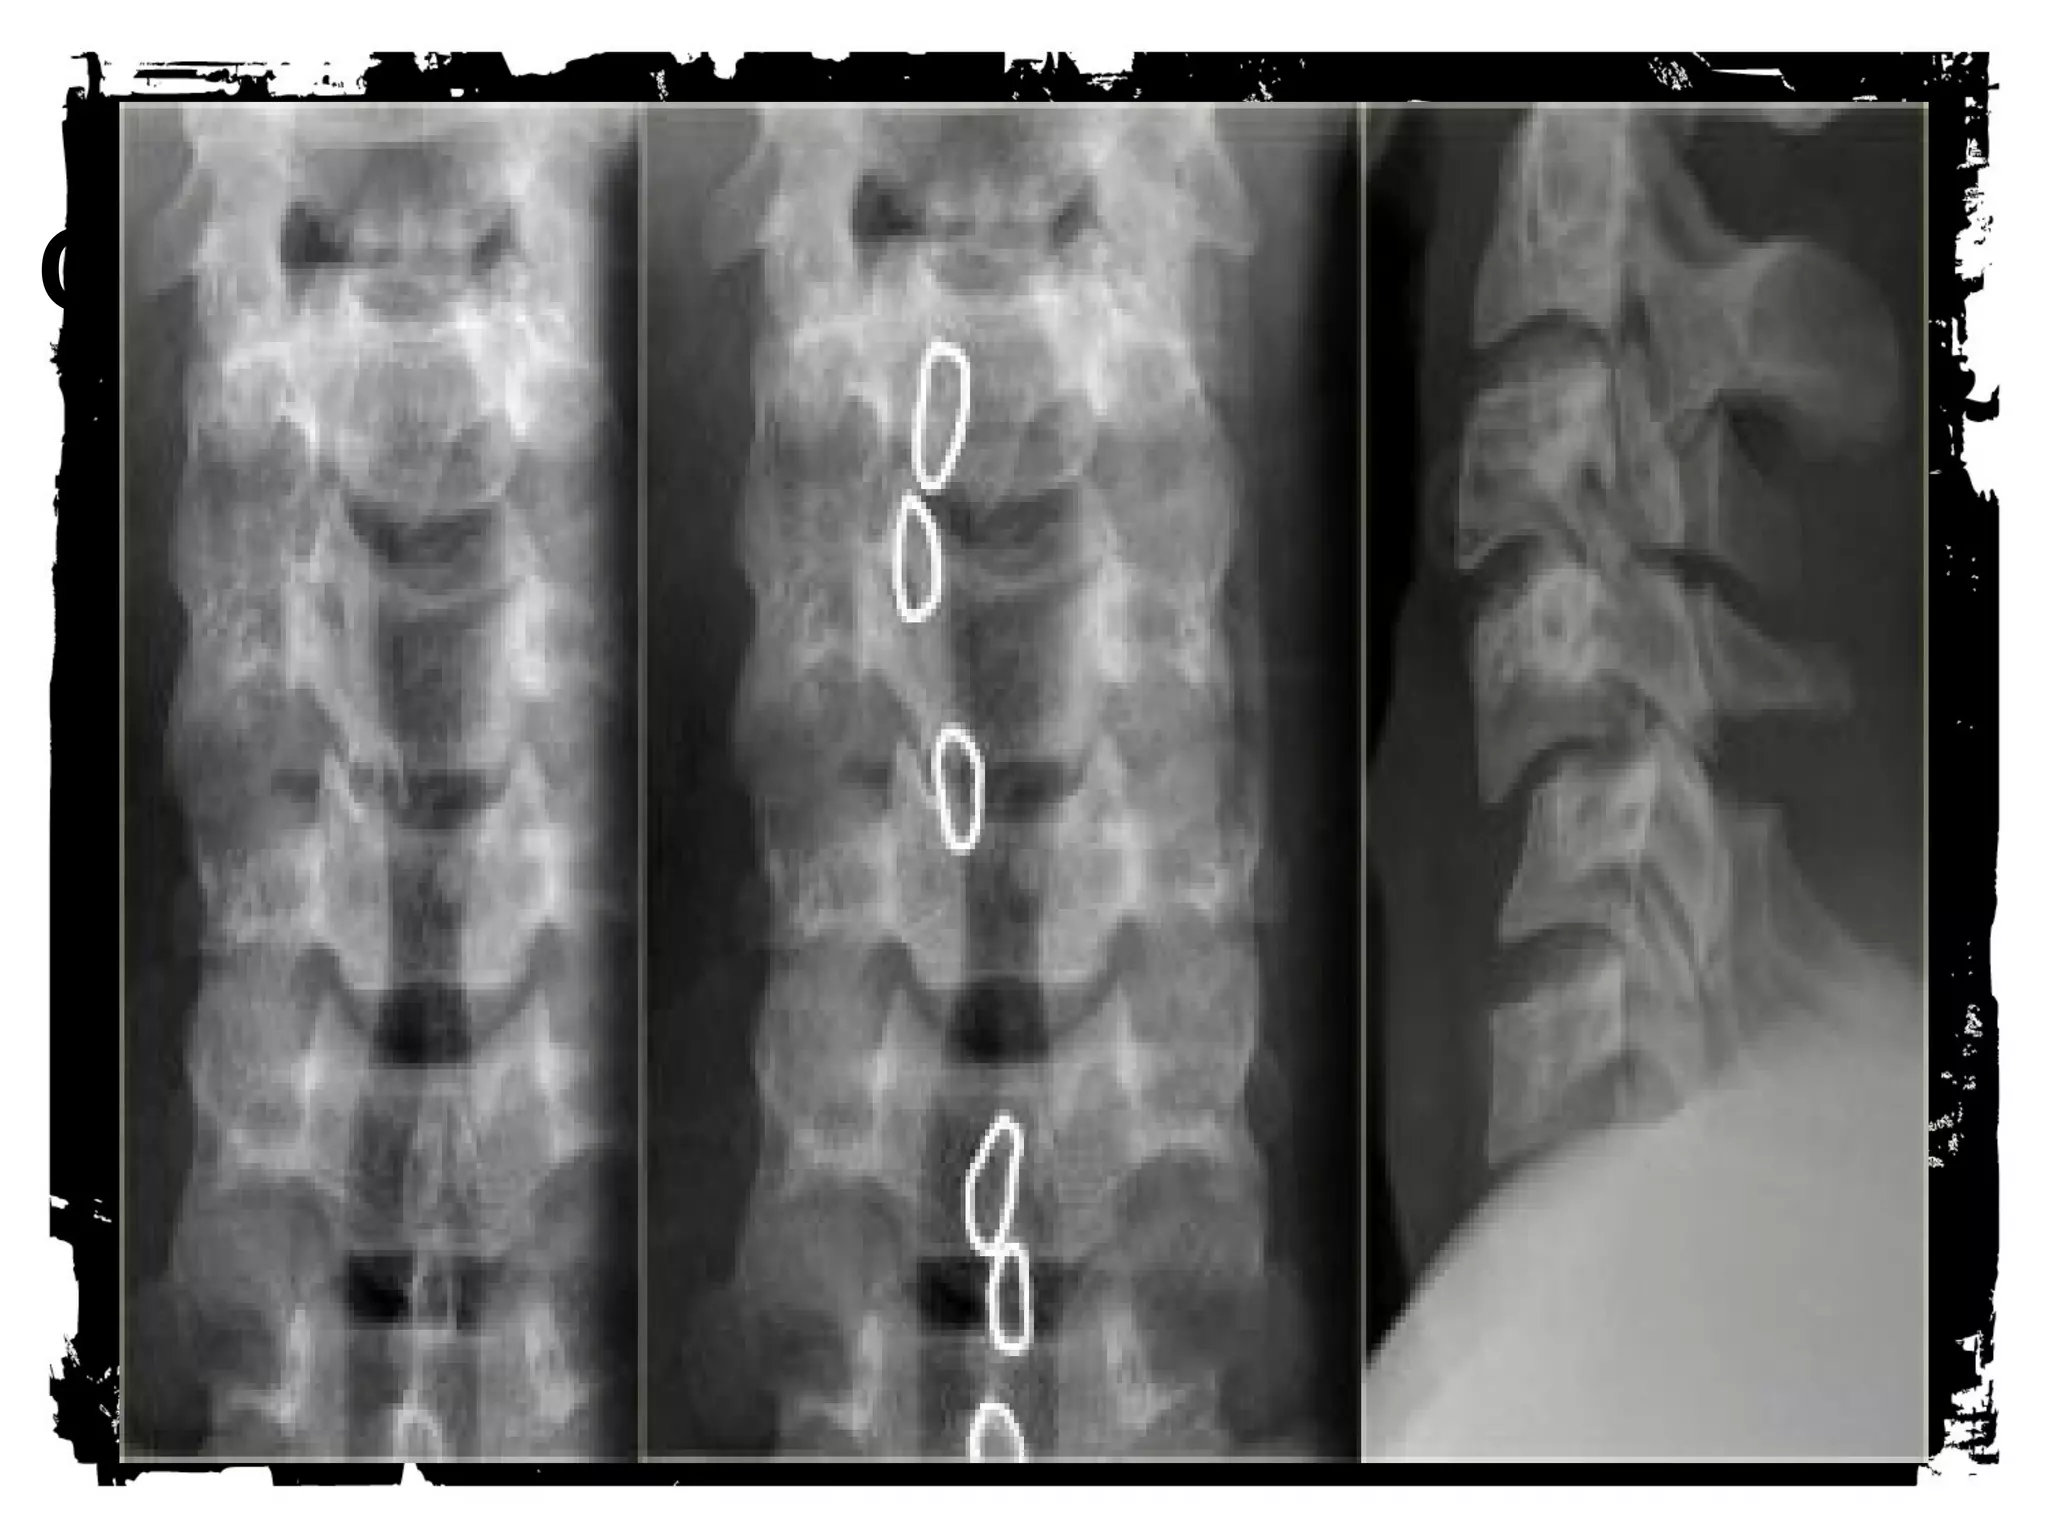

Thoracic Spine Injuries

Rigid

Spinal canal narrower than cervical or lumbar spine

Large spinal cord diameter relative to canal

diameter increases the risk of cord injury

Injury, usually significant (complete), less common

than in other regions

Association between fractures of the thoracic spine

and severe pulmonary injuries, mediastinal

hemorrhage

CLICK HERE TO ADD TEXT

Compression fracture

Injury to anterior column due to anterior or lateral

flexion

Middle and posterior columns remain intact

X-ray - decreased height anterior vertebral body, post

body height normal

Amount of anterior compression usually less than

40% of post body height

Clinically - stable, cord injury rare